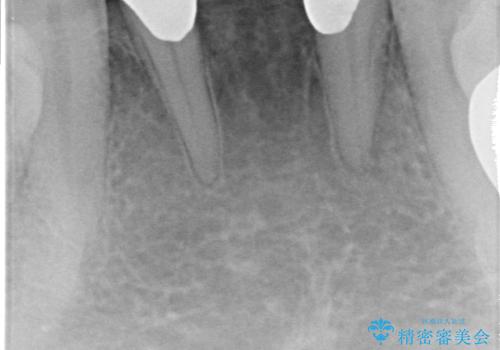

- 前歯の保険のブリッジが欠けてしまっているのを治したいとのことでした。

前装冠が剥がれていて、下の金属が見えてしまっていました。

かみ合わせもきつく、ジルコニアクラウンではセラミックでも欠けてしまいそうでした。

今回は、丈夫な欠けにくいフルジルコニア(ヴェレッツァ)クラウンでブリッジにすることにしました。